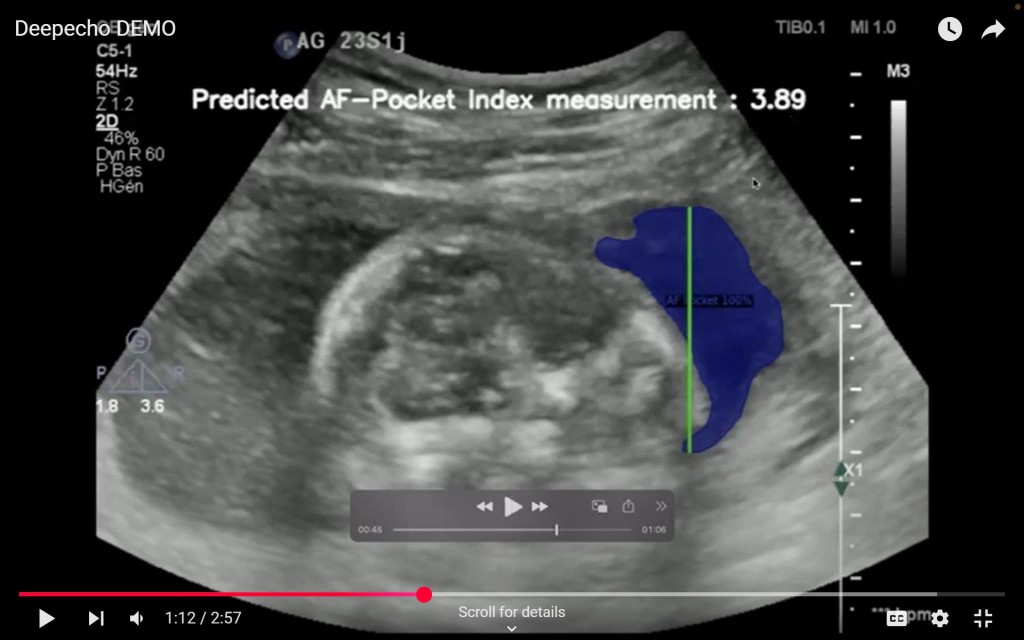

AAIC Investment Pte. Ltd.(本社:シンガポール、代表:椿 進、以下「AAIC Investment」)が運営するアフリカのヘルスケア分野に特化した投資ファンド「Africa Innovation & Healthcare Fund II(以下、AHF2号)」を通じて、DeepEcho(本社:モロッコ、CEO:Youssef Bouyakhf)へ出資しました。 DeepEchoは、AIを搭載した胎児超音波解析プラットフォームを開発・提供しています。また、同社は、2025年6月に米国食品医薬品局(FDA)より510(k)※クリアランスを取得しました。自社のAIが臨床現場レベルで95%以上の認識精度を実現していると公表しており、熟練した医療従事者と同等の信頼性を備えていることを示しています。今回の認可により、米国市場での製品販売と導入が可能となるだけでなく、その技術の安全性と有効性が国際的に認められたことを意味します。今後、医療人材が不足するアフリカをはじめとするグローバルサウスにおける普及に向け、重要なマイルストーンとなります。 DeepEchoのAI技術は、胎児の頭部や腹部、羊水などの各部位を映した超音波画像をリアルタイムで自動的に認識・分類するもので、診断に必要な“標準ビュー”を瞬時に特定します。世界最大級の胎児超音波画像データを学習に活用しており、医師による診断の精度向上と作業の効率化に貢献しています。また、構造を明確に区別するセグメンテーション処理により、より標準化された解析が可能です。 同社は、Googleが主催するスタートアップアクセラレーター「AI First MENA & Turkey」にも選出されるなど、国際的にも高く評価されています。現在提供中の標準ビュー認識および自動解析機能に加え、次世代技術としては新たなバイオマーカーをAIで同定し、子癇前症(preeclampsia)などの複雑な妊娠合併症の早期予測を目指しています。これにより、早期の医療介入と母子の健康改善が期待されます。 さらに同社は、日系企業との連携機会も積極的に模索しており、2025年8月に横浜で開催されるTICAD(アフリカ開発会議)に合わせて、CEOの来日を予定しています。

デモ写真:同社提供